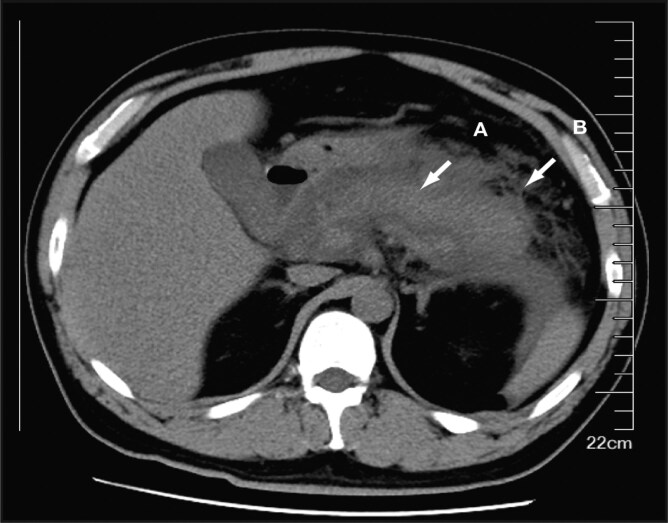

Introduction: Severe acute pancreatitis is a life-threatening condition characterized by systemic inflammatory response syndrome and an increased risk of complications such as venous thrombosis, all of which contributes to a high mortality rate. Heparin resistance, although rare, can lead to ineffective anticoagulation and thrombus formation during unfractionated heparin therapy, complicating management.

Methods: We report a case of heparin resistance in which, despite increasing the unfractionated heparin dosage, the patient's activated partial thromboplastin time remained subtherapeutic.

Results: Laboratory findings indicated normal antithrombin levels but undetectable anti-Xa activity, confirming non-antithrombin-mediated heparin resistance. A multidisciplinary approach led to the successful management of thrombosis with rivaroxaban, resulting in substantial clinical improvement.

Discussion: This case highlights the importance of early recognition and management of heparin resistance in patients with severe acute pancreatitis. Combined monitoring of activated partial thromboplastin time and anti-Xa activity is crucial for optimizing anticoagulation therapy and preventing complications such as deep vein thrombosis.